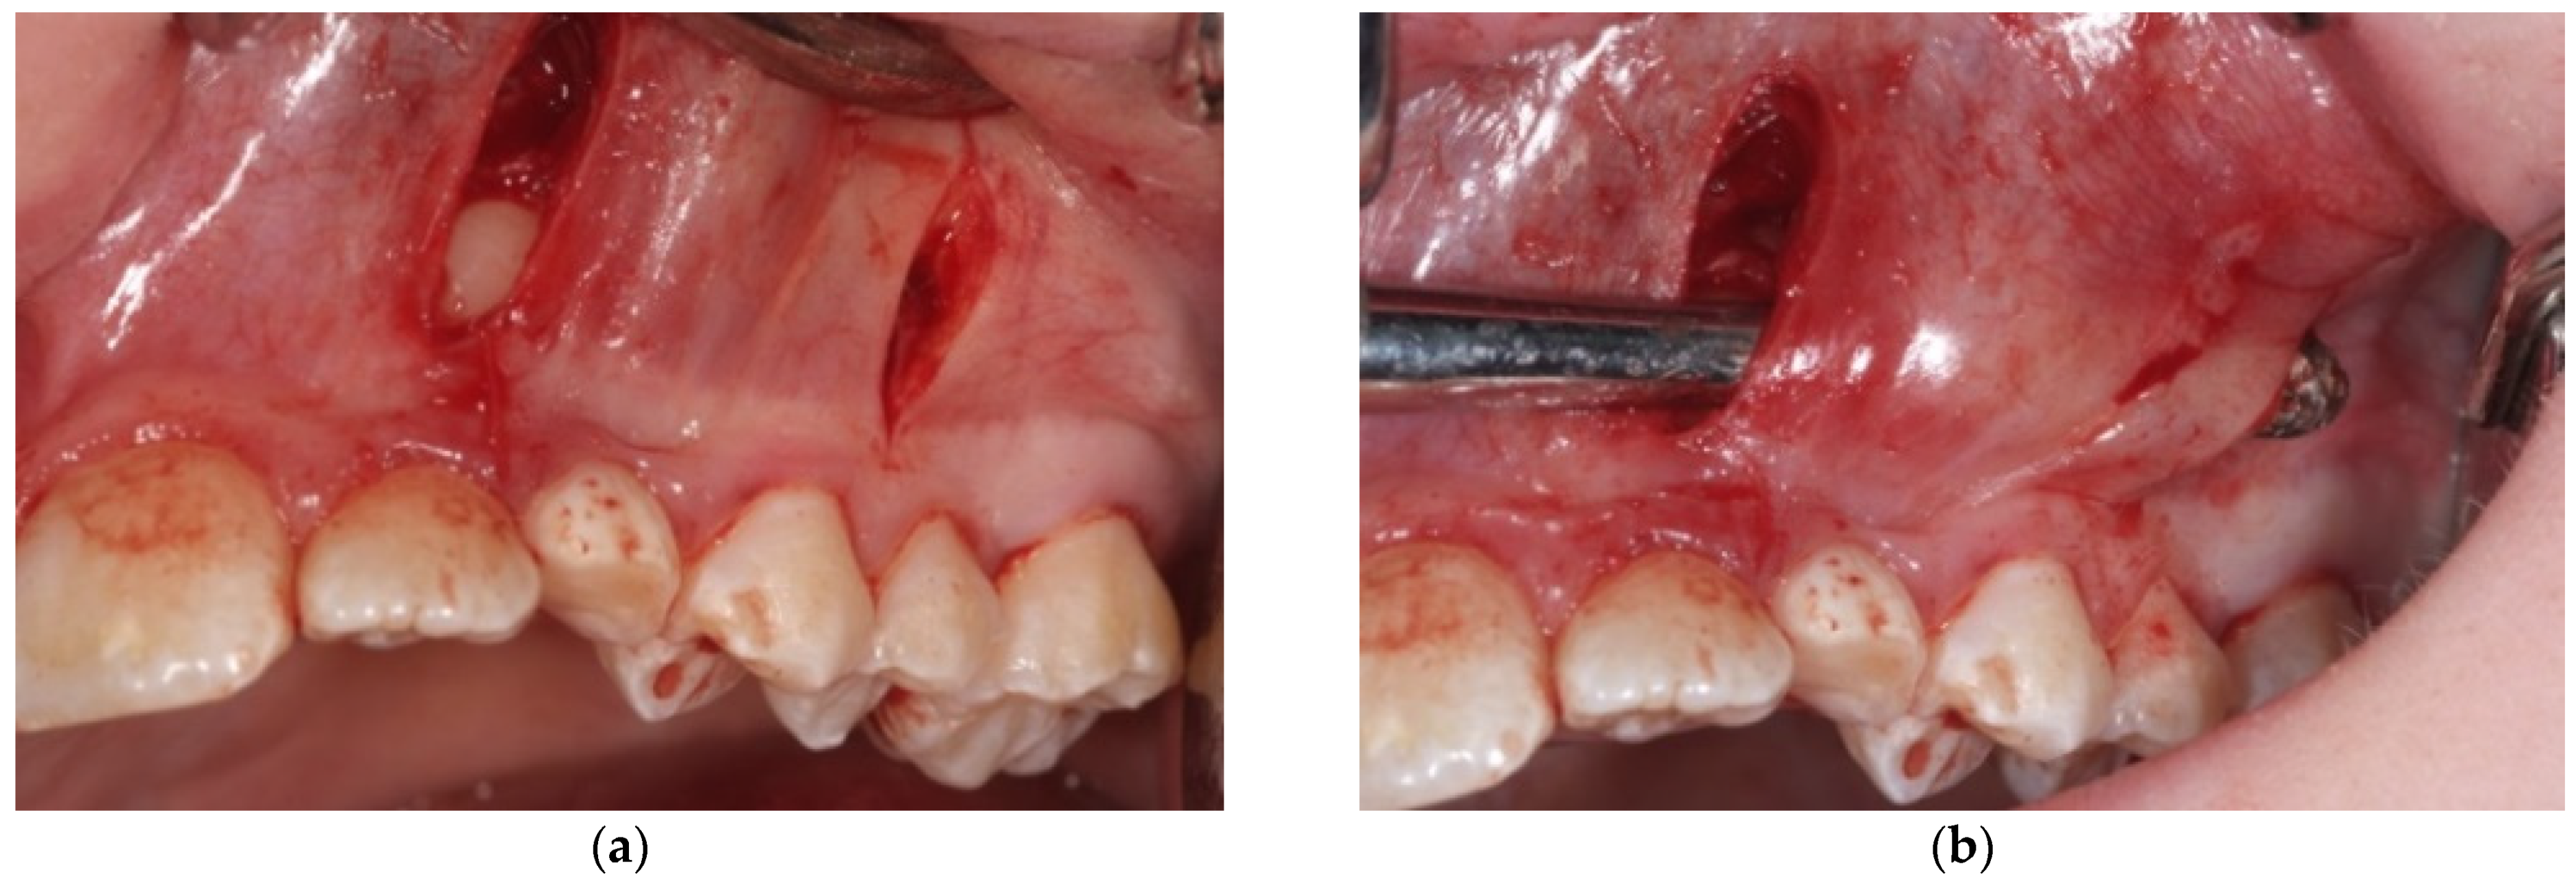

- A first vertical incision, at the level of the impacted tooth crown, and its exposure, with a periosteal elevator, are then performed. If a bony cortex is present overlying the crown, a small bony cavity is made using the multi-blade conical burr with a low-speed right-angle handpiece to expose all of the canine’s crown surface (Figure 3). In any case, a thin groove must be present peripherally to the canine’s crown to guarantee a good isolation from bleeding. Moreover, a further ostectomy is performed on the tooth side toward which the orthodontic traction will be performed (traction route);

- A second vertical incision is made between the first and second premolar, and the sub-periosteal tunnel is created with a periosteal elevator to connect the two incisions from front to back (Figure 4);